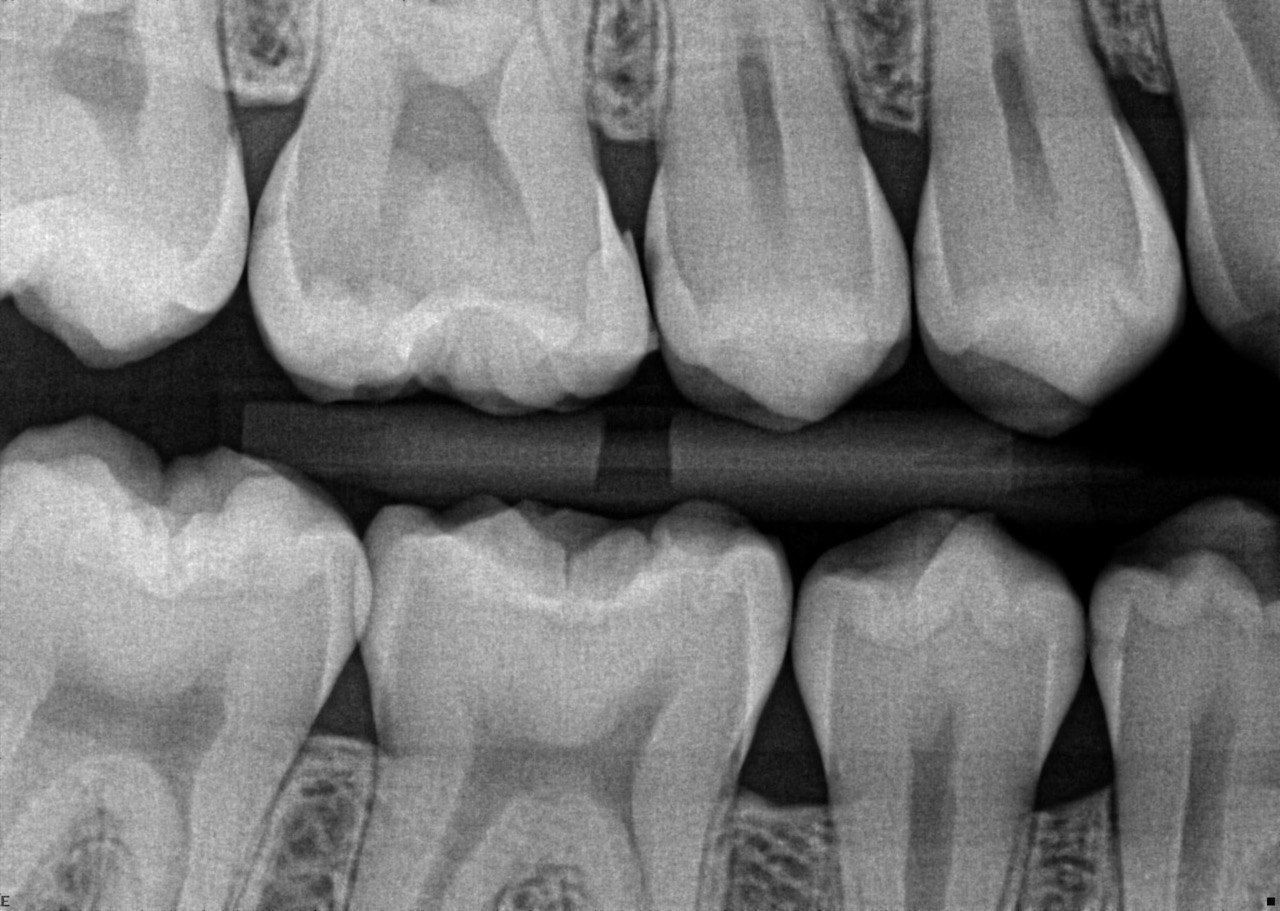

Quistion 11: What are the conditions of the distal and mesial surfaces of the tooth # 4.5 respectively?

Question 12: What option can describe the mesial surface of the tooth # 3.7?

Question 13: What option can describe the mesial surface of the tooth # 3.8?

Question 14: What option can describe the mesial surface of the tooth # 3.4?

Question 15: What option can be selected for treatment of the caries in mesial surface of the tooth # 3.4?